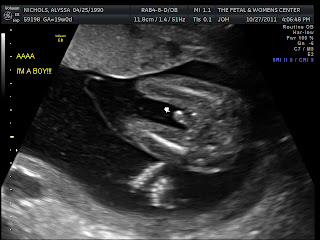

Boy!

You can tell which baby is which by a letter A or B on the left of the picture.

We finally got to the facility and we sat there for about an hour before we got called back. I could not stop fidgeting or moving around because i was so excited to know what they were already! We were finally got called back and we jumped out of our seats. We raced back to the back and they quickly started the ultrasound. The tech started doing her thing and examined a few things before going onto the gender. Then she pointed to the boy part on baby A (who might i add, was spreading his legs and throwing it in our view for visibility. It was hilarious) and it was definitely a baby boy! My heart sank and Trevor and I were both overwhelmed with happiness! We were having boys!! Since we confirmed the first baby was a boy, we assumed the other one was a boy too since they are identical, but we still wanted to check in case. The tech did some more examinations on the first baby and then finally went on to the next one. Then there it was! The baby boy part again! Both of our boys liked showing off their parts to us and were not shy at all! It was seriously the funniest thing ever. Of course Trevor was SUPER proud of them. haha.